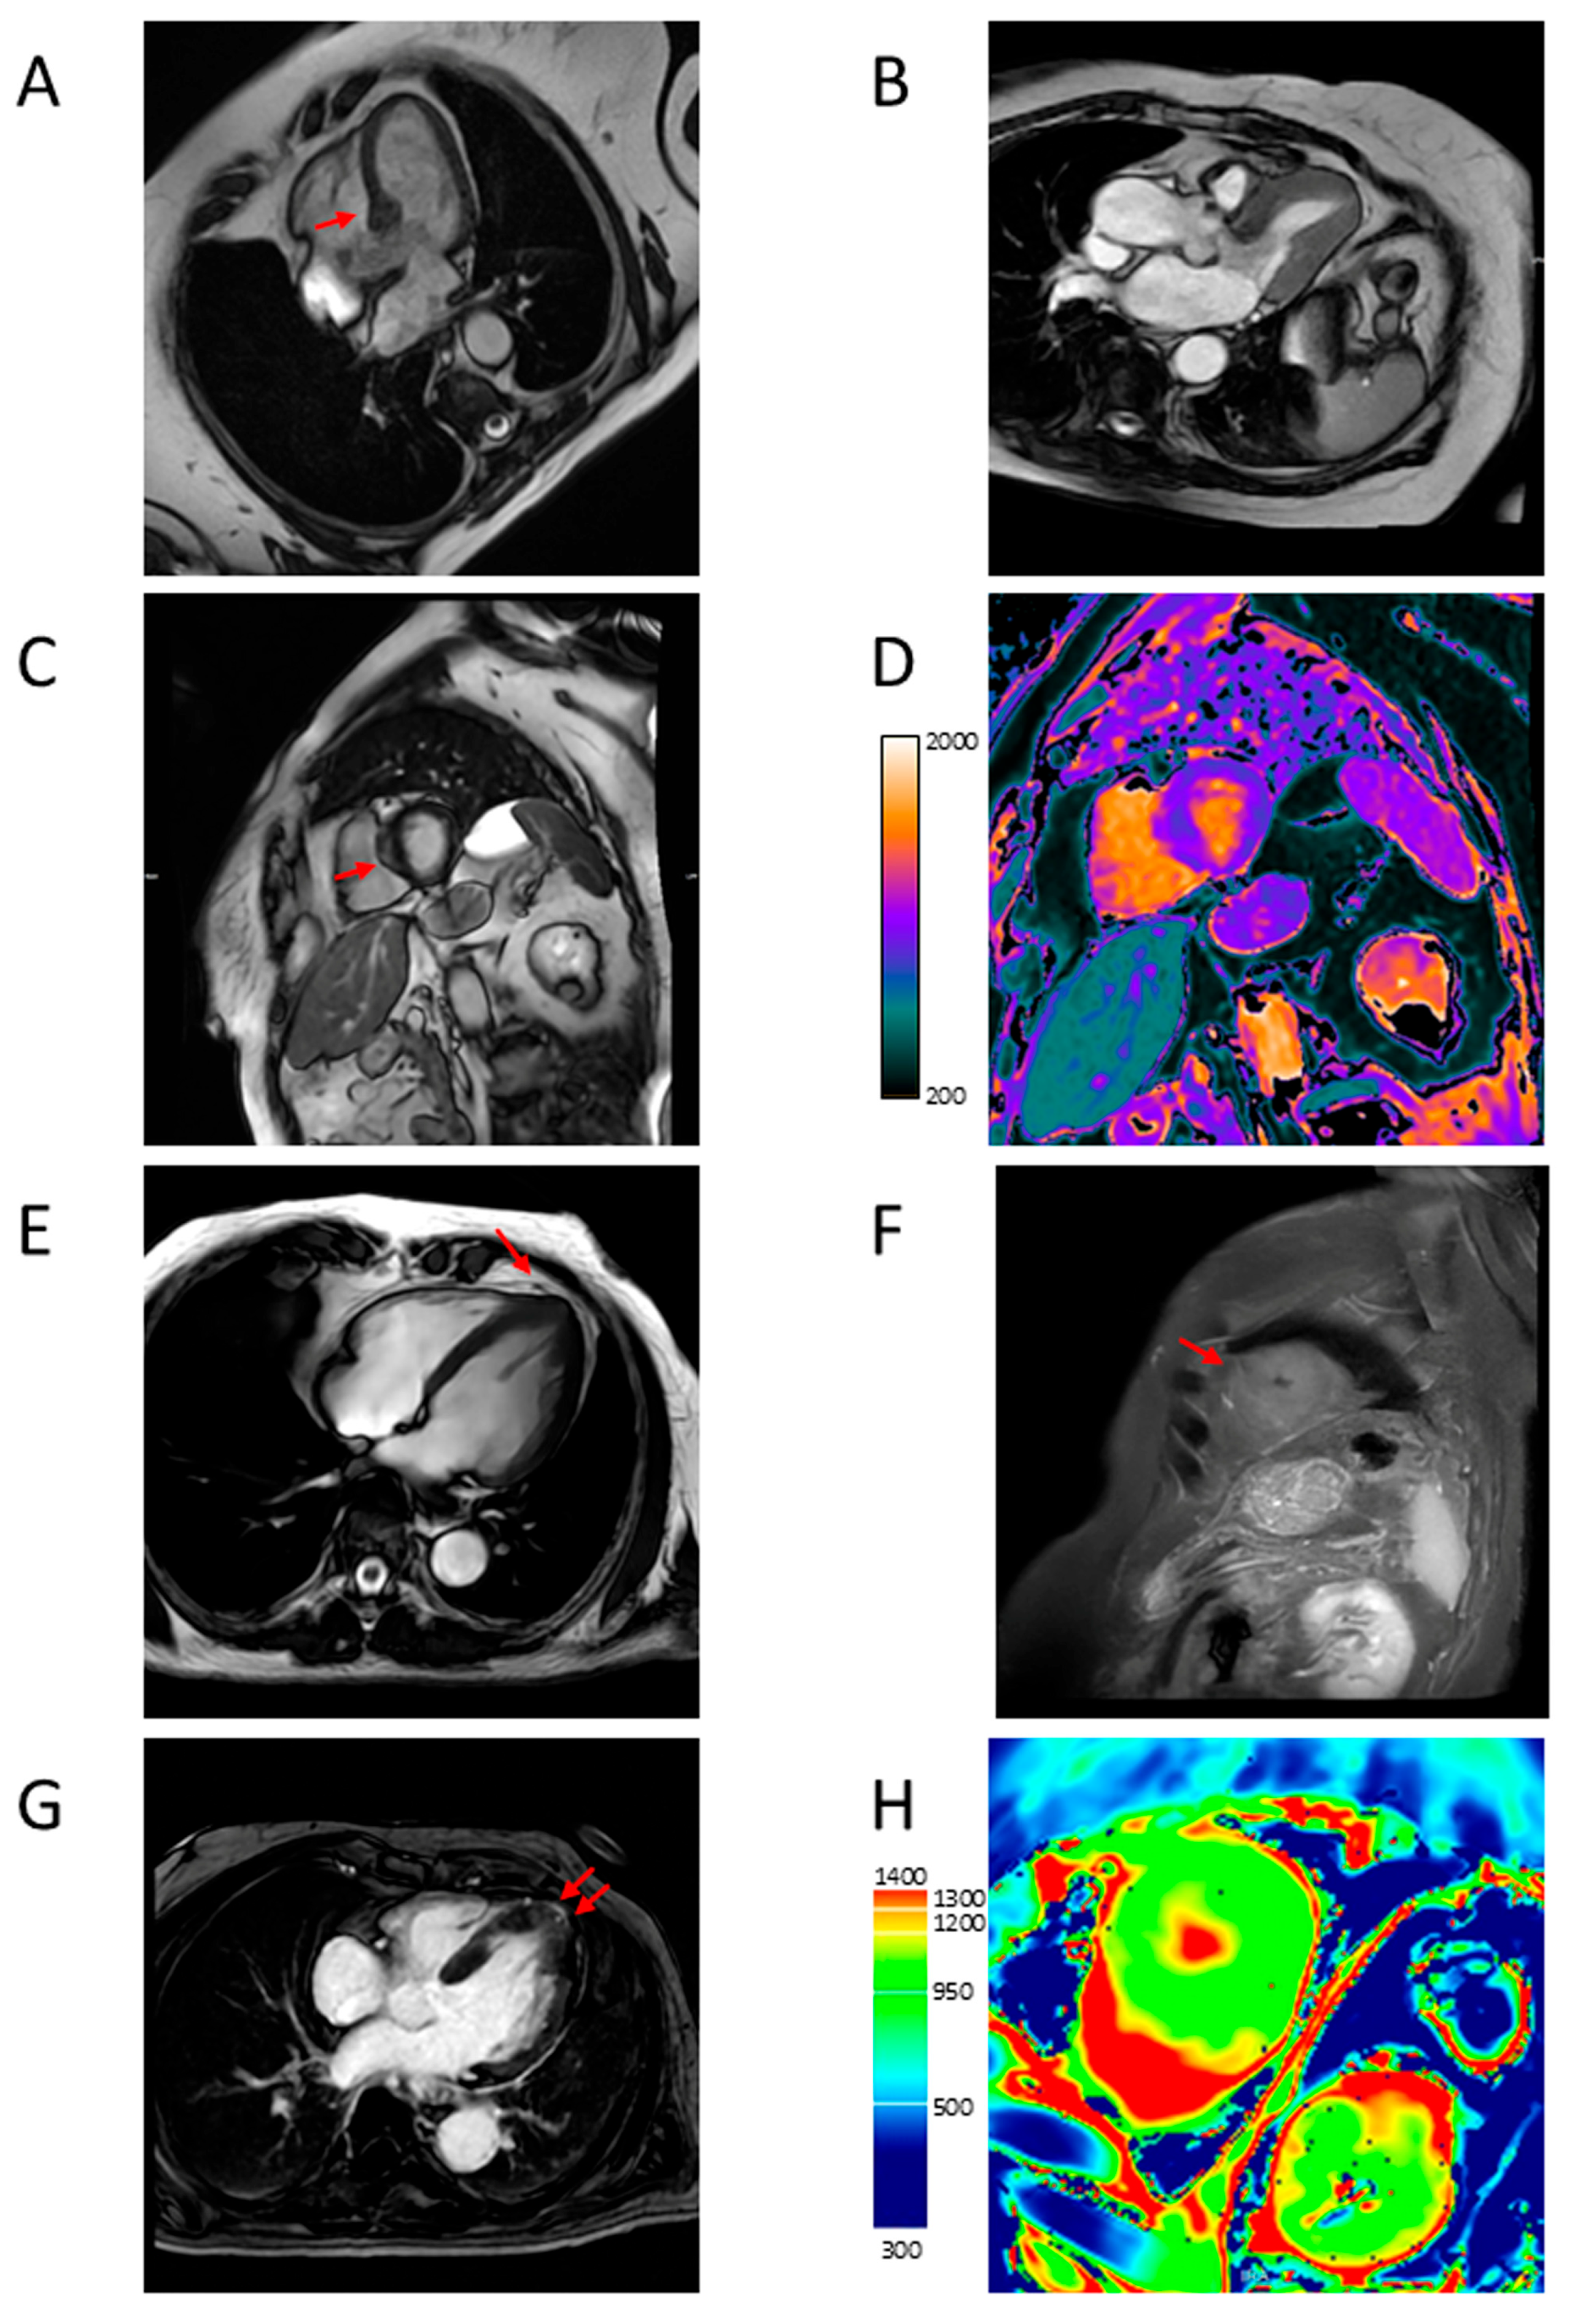

4.2. Apical Aneurysm

4.3. LVOTO

4.4. LV Function

4.5. Myocardial Fibrosis

4.6. Microvascular Dysfunction